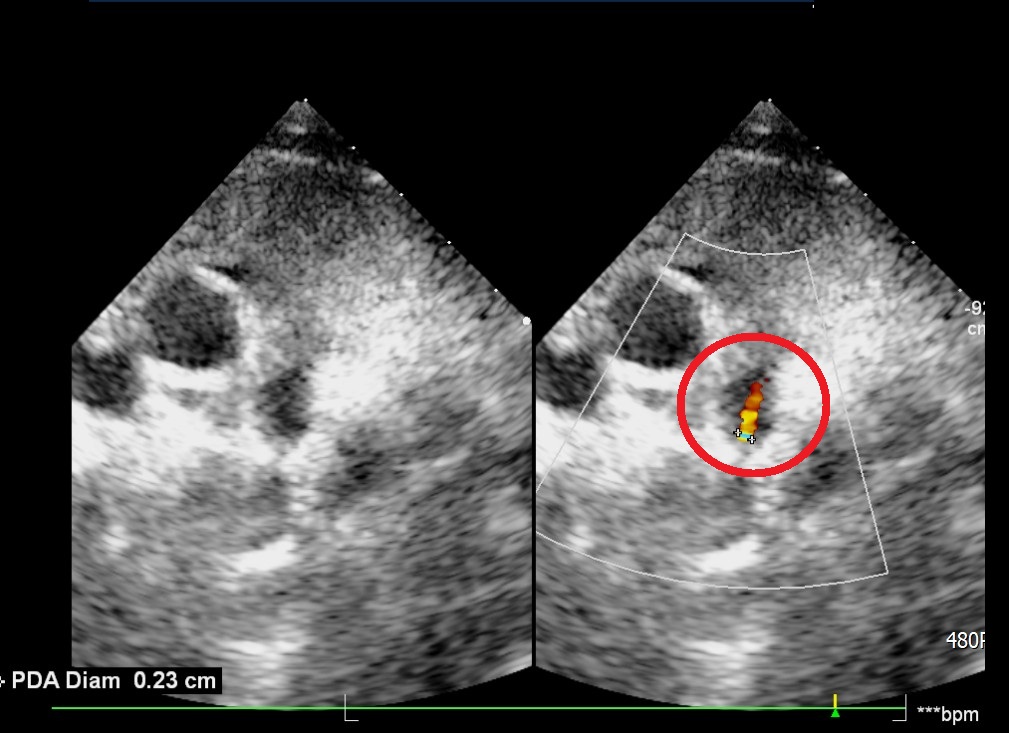

一名7歲女童因連續發燒、腹痛及嘔吐急診就醫,確診為B型流感。因擔心引發心肌炎,醫師安排住院觀察,沒想到透過心臟超音波檢查,意外發現女童患有「開放性動脈導管(PDA)」,這才解開了她長期胸悶、呼吸不順的真相。隨後,由大千綜合醫院小兒心臟科詹裕仁醫師與台中榮民總醫院總院長傅雲慶強強聯手,順利完成苗栗縣首例「兒童心導管微創關閉手術」。術後女童鼠蹊部傷口僅0.2公分,隔天即康復出院,寫下苗栗醫療新里程碑。

女童接受心臟超音波檢查時,發現有開放性動脈導管問題(紅圈處) 照片:大千綜合醫院供